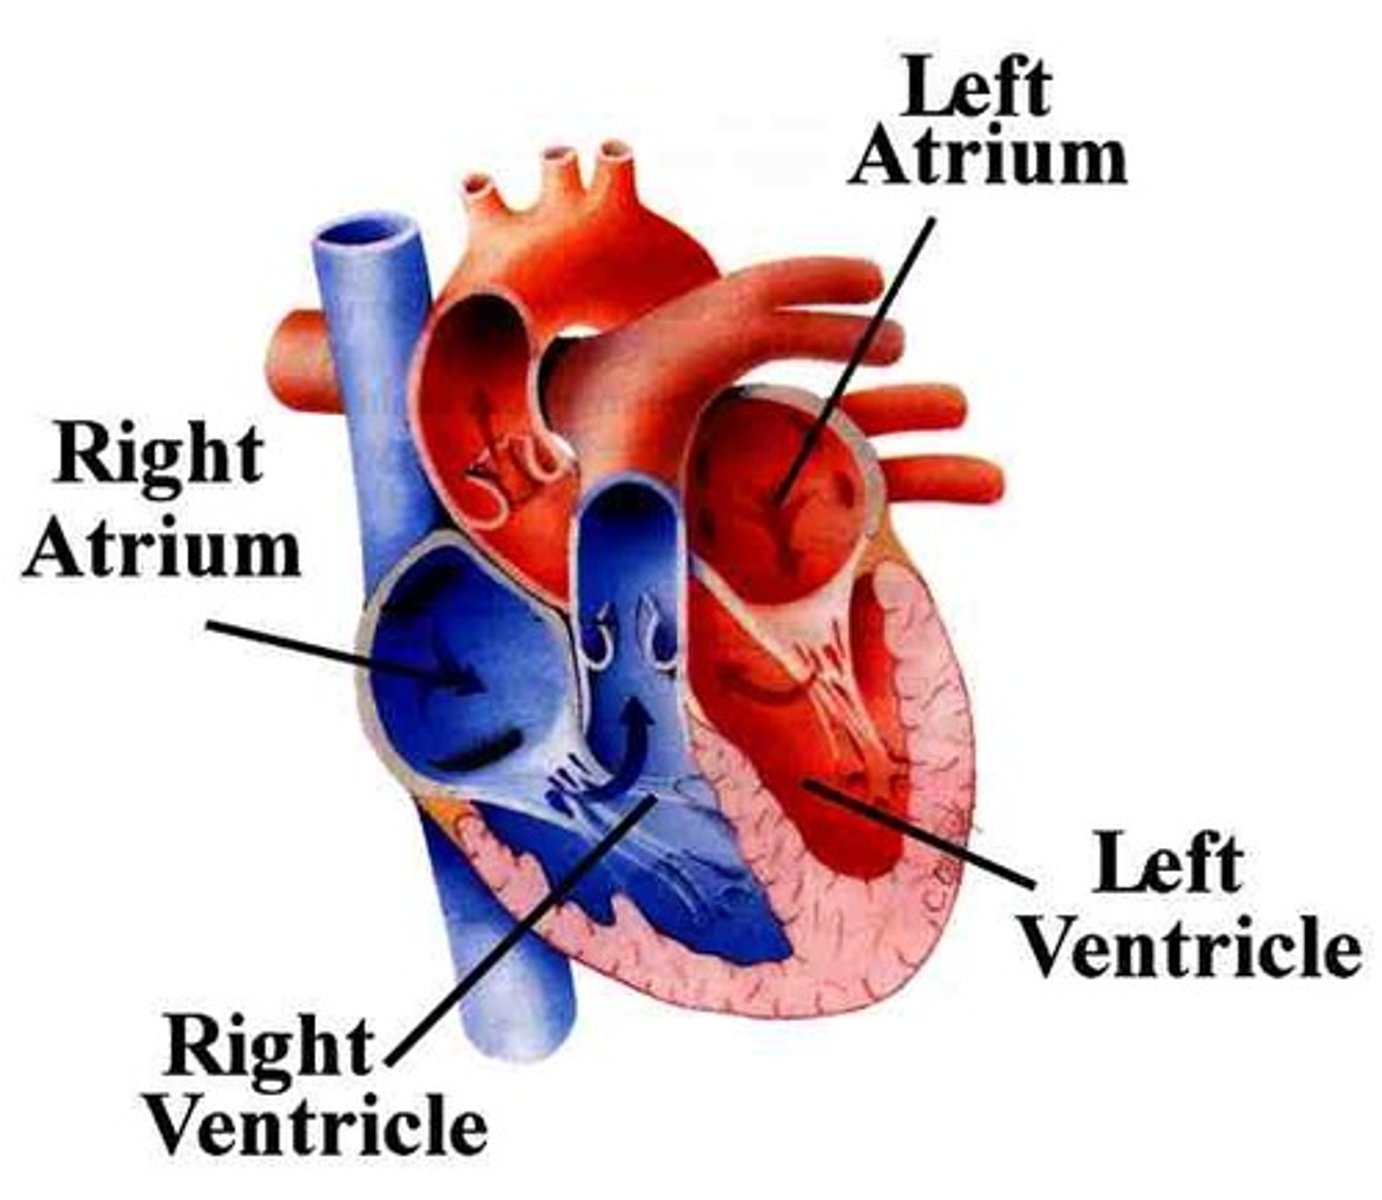

Two atria; right and left (receiving chambers)

Two ventricles; right and left (discharging chambers)

Name the four chambers

From: Left atrium through the bicuspid valve

To: Aorta through semilunar valve to systemic system

The left ventricle receives blood from:

and sends it:

From: Right atrium through tricuspid valve

To: Pulmonary trunk (artery) through semilunar valve to lungs then pulmonary veins

The right ventricle receives blood from:

and sends it: